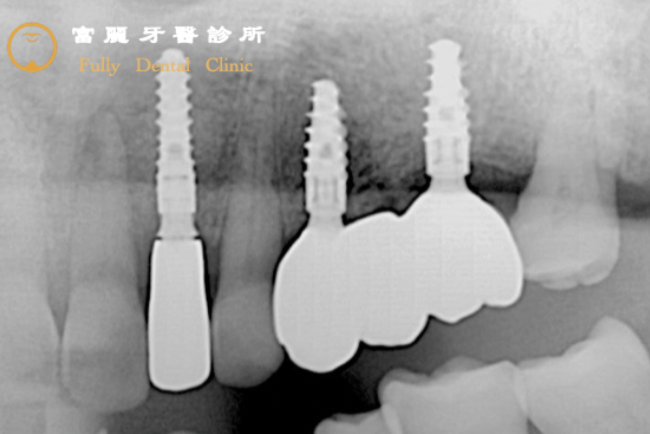

案例3

Before

牙根斷裂且包覆牙根的骨頭(灰色網狀)被細菌破壞(黑色的範圍),牙齒會開始出現晃動無法支撐咬合,尤其發生在對咬合功能十分重要的大臼齒,造成患者的咀嚼能力大大降低,因此決定以植牙來恢復!

After

將牙根移除後,先填補上人工骨粉,讓剩餘的骨頭沿著人工骨粉生長回來;在缺牙處植入人工牙根(透過3D植牙導航儀植入深螺旋高階植體),再裝上擬真全瓷牙冠復形,以高穩定度與高強度的人工牙根和牙冠修復咬合功能,不受缺牙所苦!